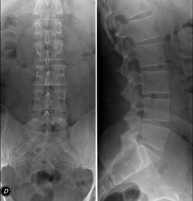

- RX Columna lumbar

Técnica mediante la cual, utilizando rayos X, se obtienen imágenes de la columna lumbar para su estudio. Indicaciones: ciática, traumatismo, dolor lumbar.

- Telerradiología columna

Técnica mediante la cual, utilizando rayos X, se obtienen imágenes de toda la columna vertebral para su estudio, valorando especialmente la presencia de escoliosis y dismetrías pélvicas.